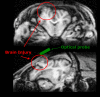

In this study, we used diffuse optics to address the need for non-invasive, continuous monitoring of cerebral physiology following traumatic brain injury (TBI). We combined frequency-domain and broadband diffuse optical spectroscopy with diffuse correlation spectroscopy to monitor cerebral oxygen metabolism, cerebral blood volume, and cerebral water content in an established adult swine-model of impact TBI. Cerebral physiology was monitored before and after TBI (up to 14 days post injury). Overall, our results suggest that non-invasive optical monitoring can assess cerebral physiologic impairments post-TBI, including an initial reduction in oxygen metabolism, development of cerebral hemorrhage/hematoma, and brain swelling.